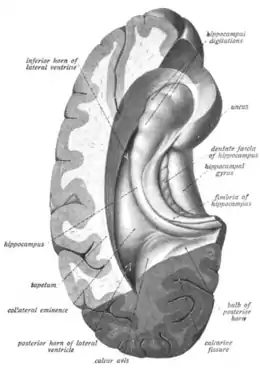

The hippocampus can be seen as a ridge of gray matter tissue, elevating from the floor of each lateral ventricle in the region of the inferior or temporal horn.[17][18] This ridge can also be seen as an inward fold of the archicortex into the medial temporal lobe.[19] The hippocampus can only be seen in dissections as it is concealed by the parahippocampal gyrus.[19][20] The cortex thins from six layers to the three or four layers that make up the hippocampus.[21]

The hippocampus, including the dentate gyrus, has the shape of a curved tube, which has been compared to a seahorse, and to a horn of a ram, which after the ancient Egyptian god often portrayed as such takes the name cornu Ammonis. Its abbreviation CA is used in naming the hippocampal subfields CA1, CA2, CA3, and CA4.[20] It can be distinguished as an area where the cortex narrows into a single layer of densely packed pyramidal neurons, which curl into a tight U shape. One edge of the "U," – CA4, is embedded into the backward-facing, flexed dentate gyrus. The hippocampus is described as having an anterior and posterior part (in primates) or a ventral and dorsal part in other animals. Both parts are of similar composition but belong to different neural circuits.[22] In the rat, the two hippocampi resemble a pair of bananas, joined at the stems by the commissure of fornix (also called the hippocampal commissure). In primates, the part of the hippocampus at the bottom, near the base of the temporal lobe, is much broader than the part at the top. This means that in cross-section the hippocampus can show a number of different shapes, depending on the angle and location of the cut.

In a cross-section of the hippocampus, including the dentate gyrus, several layers will be shown. The dentate gyrus has three layers of cells (or four if the hilus is included). The layers are from the outer in – the molecular layer, the inner molecular layer, the granular layer, and the hilus. The CA3 in the hippocampus proper has the following cell layers known as strata: lacunosum-moleculare, radiatum, lucidum, pyramidal, and oriens. CA2 and CA1 also have these layers except the lucidum stratum.[23][24]